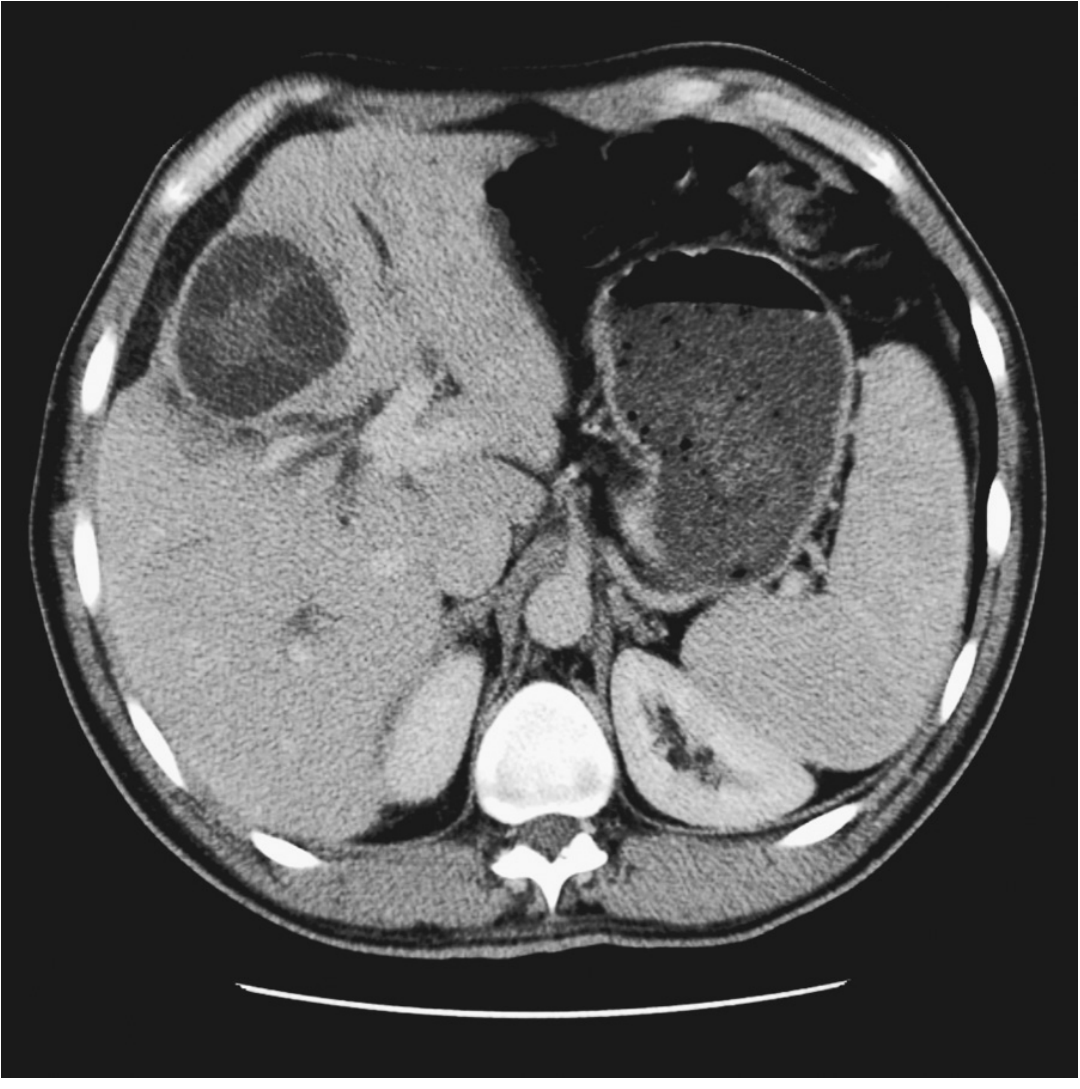

CT / MRI

CT scan showing hydatid cyst in right lobe of liver

Fig. CT showing typical hydatid cyst in right hepatic lobe. — Sleisenger & Fordtran's Gastrointestinal and Liver Disease

• Avascular cysts with ring enhancement

• Multiple daughter cysts with intracystic septations

• Peripheral focal calcifications

• Fluid density varies with proteinaceous debris

• Better than US for extrahepatic disease and hepatic anatomic relationships